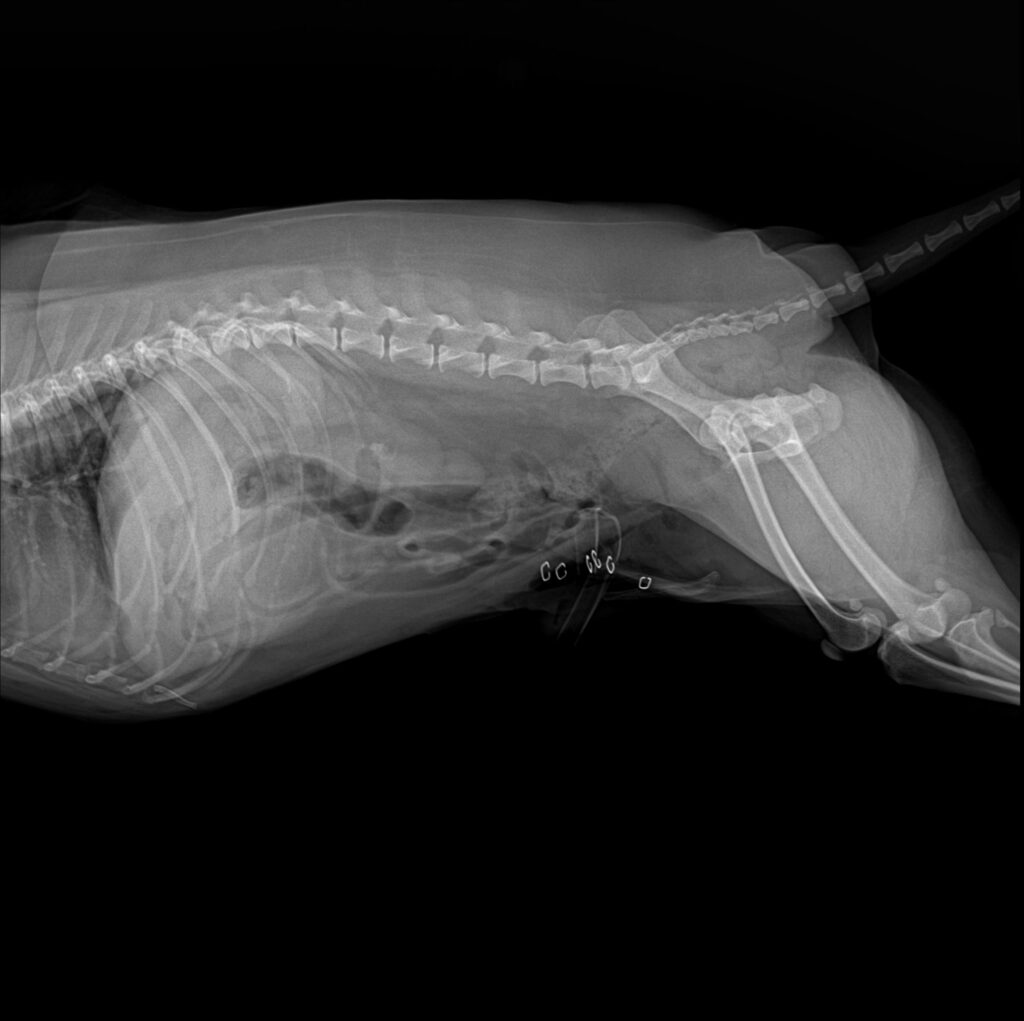

엑스레이 검사

엑스레이 검사에서 방광 내부에 다수의 방광 결석이 뚜렷하게 확인되었습니다. 다행히 요도 내 결석은 관찰되지 않아 급성 요로 폐색 소견은 없는 상태였습니다.

환자의 수술 전 방사선 사진/ 출처: 미래동물의료센터